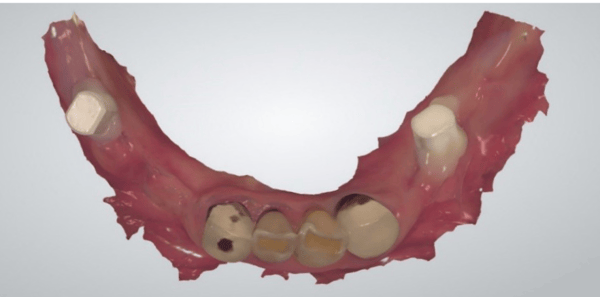

一位長期受牙齒問題困擾的病患走進了診間,他的下顎依賴著一副活動局部假牙維持僅存的咀嚼功能,而右下側的牙橋邊緣已出現繼發性齲齒,多顆牙齒根尖甚至出現病變。對於任何一位經驗豐富的醫師來說,這都是一個棘手的開局。病患渴望植牙,但他提出了一個令許多醫師頭痛的要求:受限於經濟與社交需求,他不願意拔除所有患牙,更不願意在漫長的治療期間經歷無牙的尷尬期。

在數位化介入之前,你可能需要花費大量時間與技工所溝通,反覆進行藻膠印模來確認咬合垂直高度。Jaemin Lee 醫師最初制定了一個穩健的兩階段計畫:先處理左下顎的植牙,保留右側牙橋與 RPD 作為過渡。這是一個合理的打法,透過數位掃描記錄下初始的咬合狀態與軟組織型態,為這場長跑做好了準備。這時,數位檔案就像是一個精準的時空膠囊,完整保存了病患未經破壞前的口腔資訊,這在後續的突發狀況中發揮了決定性的作用。

就在第一階段治療開始五週後,計畫趕不上變化。病患那副原本就脆弱的 RPD 徹底斷裂,且已無法修復。這意味著病患面臨著徹底喪失咀嚼功能的風險,恐懼與焦慮瞬間籠罩了整個醫病關係。在傳統流程中,這通常代表著災難:你需要重新印模、重新製作臨時假牙,甚至被迫推翻原有的手術時程。